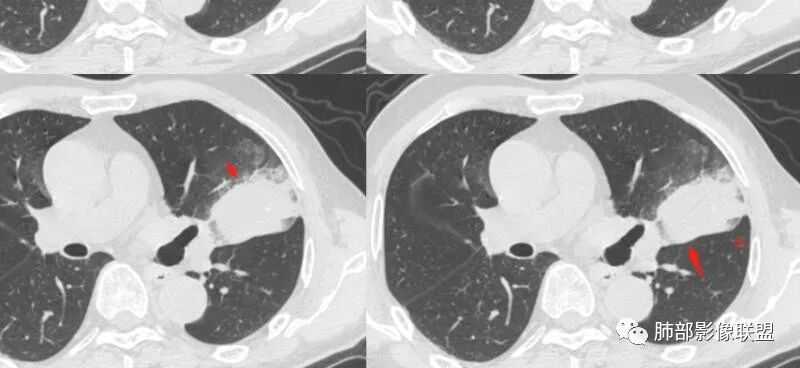

周围磨玻璃影是飘出去的粘液,也是肿瘤的一部分吧?

@小赵 这个不一定是粘液,很可能还是周围癌性浸润。看术前复查,原磨玻璃区呈明显小叶间隔增厚改变了。说明还是癌性淋巴浸润。

癌细胞气腔播散?癌性淋巴道炎?黏液?阻塞性?肺出血?

@温附一影像科,傅钢泽 应该是STA(气腔播散)加癌性淋巴管炎。

支气管稍扩张→有张力,GG0边缘清楚,局部有小叶间隔阻挡。

反思,恶性膨隆,远端空洞,强化坏死不均,里面血管似乎也是增粗,边界不清,似乎有侵犯。坏死还是边界不清。

肺炎型肺癌的基本影像学特点—南边老师总结

1、外周分布(起源外围由外朝内发展蔓延);

2、实变和磨玻璃阴影特点;

3、病理性支气管充气征;

4、实变内有密度较低、强化较低区;

5、“假空洞”/“蜂窝征”;

6、周围小结节,树芽征少;

7、血管造影征;

8、间质增厚改变;

9、瘤体显示;

10、淋巴结肿大;

11、胸膜改变:糊墙征;

12、前后对比进展:病灶增大、GGO区实变。